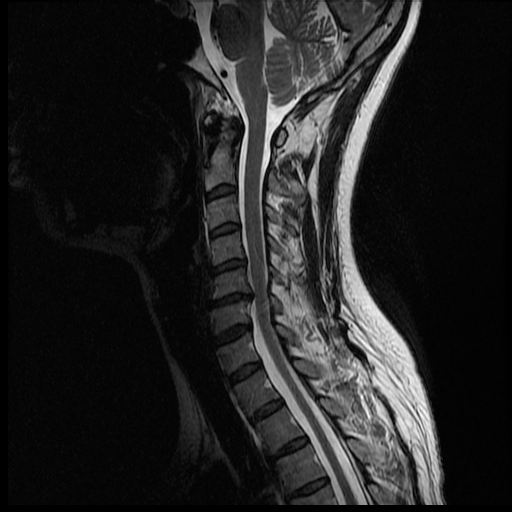

I'm waiting anxiously for Monday morning, but my husband has been pouring over the MRI images most of the night and even this morning. He's not a doctor, but it seems I may have a herniated disc. I hope this is the only thing going on.... The thing is we don't know if this is C6/C7 (where the lesion was seen), or C5/C6. Here are some of the pictures that show that the disc may be bulging/herniated.

Hopefully the experts come to the same conclusion, and that there isn't anything else... only Monday will tell.